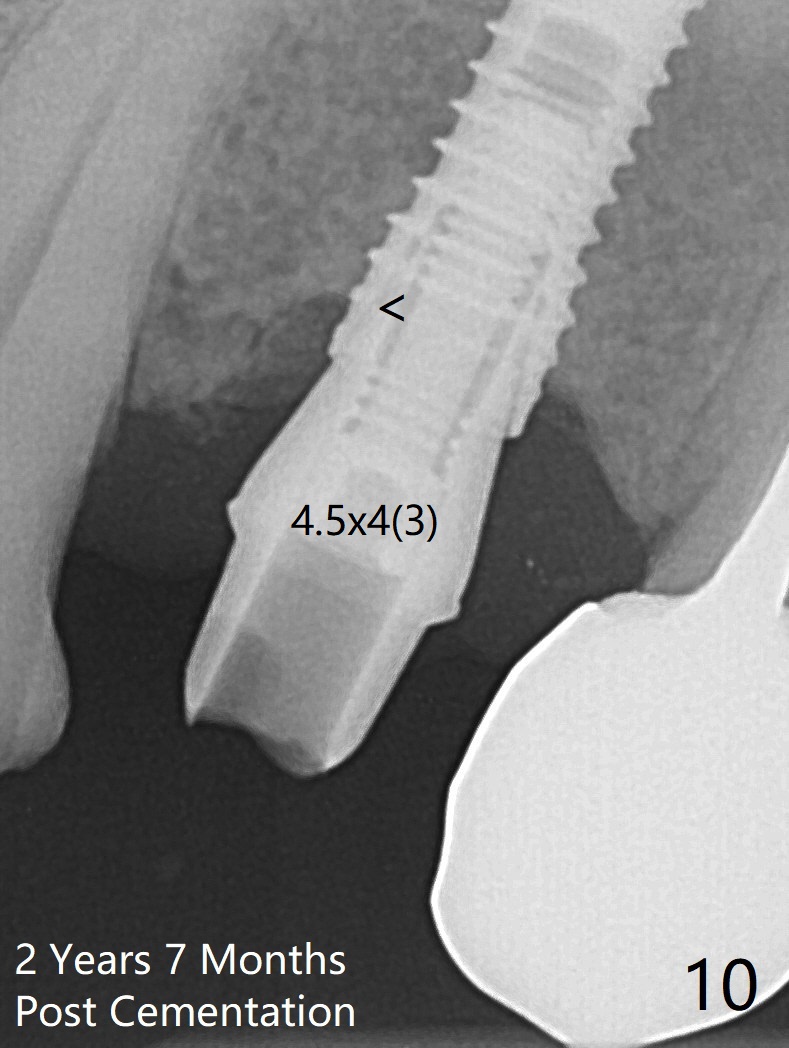

RPD Clearance